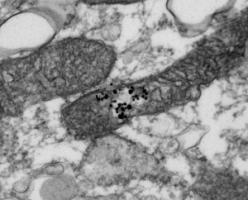

Une souris nommée TruHuX : les souris humanisées obtenues, appelées TruHuX (pour véritablement humain), possèdent un système immunitaire humain entièrement développé et pleinement fonctionnel, comprenant des ganglions lymphatiques, des centres germinaux, des cellules épithéliales humaines du thymus, des lymphocytes T et B humains, des lymphocytes B mémoire et des plasmocytes produisant des anticorps et des auto-anticorps hautement spécifiques identiques à ceux des humains.

Ces souris TruHuX développent bien des réponses en anticorps neutralisants matures contre certaines bactéries et virus testés.